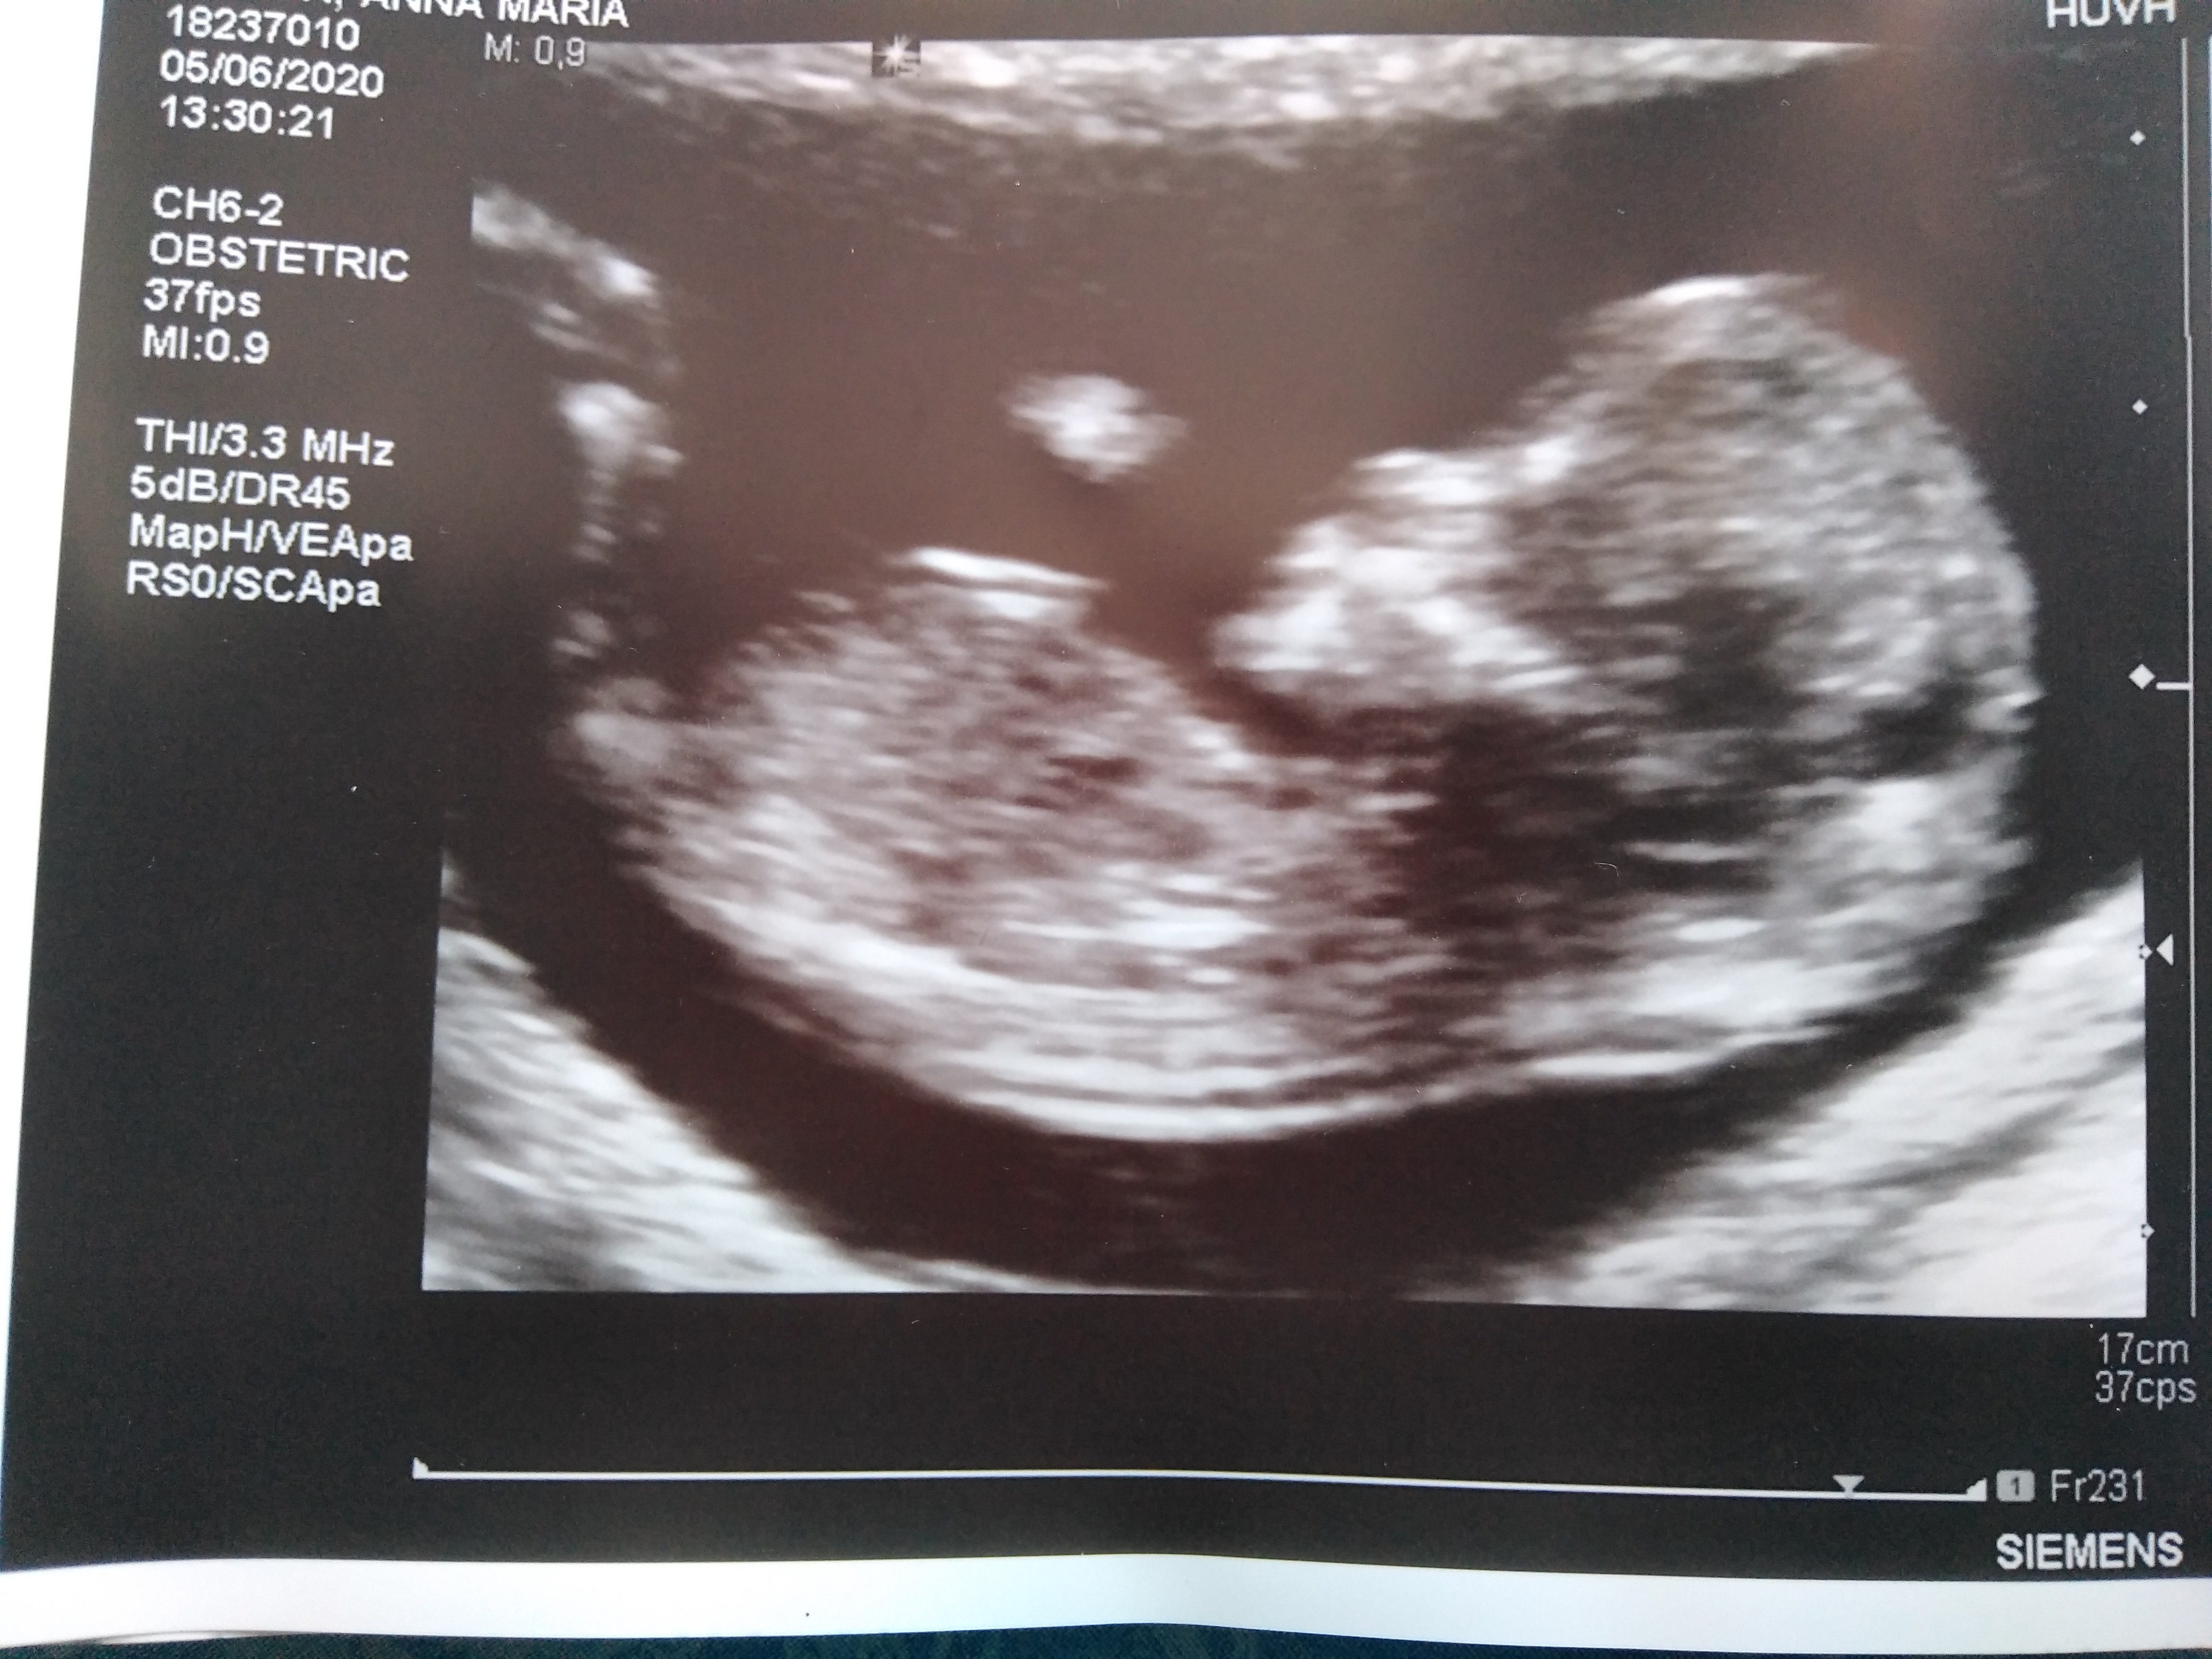

A tutaj moja kluska

ma 6,5 cm, tetno 167, i wyszlo pare dni starsze, teraz 12+6 (z OM bylo 12+1)